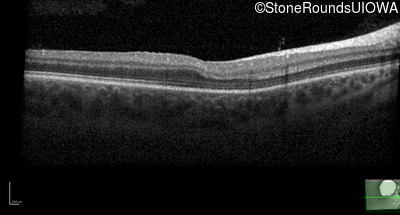

Age at visit: 6 months (Visit 5)